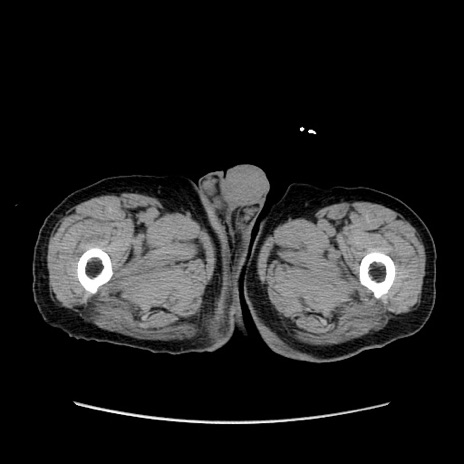

症例24(横断像)

【症例】80歳代男性

【主訴】左側腹部痛、嘔吐

【現病歴】本日早朝より左腹部に痛みあり。昼頃嘔吐認めたため、救急要請。

【既往歴】直腸癌(Mile手術)、胆摘

【身体所見】意識清明、BT 35.9℃、BP 221/93mmHg、SpO2 97%(RA) 、腹部:左ストーマ周囲に限局性の腹部膨隆あり。 膨隆部自発痛・圧痛あり・軟。

【データ】WBC 7700、CRP 0.09